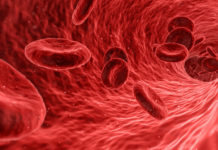

Pierwsze objawy zakrzepicy żył

Zakrzepica żył często przebiega bezobjawowo. Niestety może mieć także groźne skutki dla zdrowia i życia. Zatory najczęściej tworzą się w żyłach nóg, ale również...